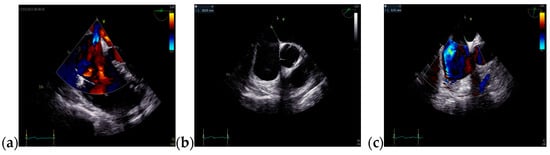

The TTE performed on admission showed a non-dilated left ventricle with an ejection fraction (EF) of 51% (using Simpson’s method), dilated right chambers, mild functional tricuspid regurgitation, mild pulmonary hypertension, tricuspid annular plane systolic excursion of 19 mm, inferior vena cava (IVC) with 18 mm diameter, and respiratory variability greater than 50%. The TTE raised the suspicion of ASD with significant hemodynamic shunt (Qp/Qs = 2.24) (Figure 2 and Figure 3).

Figure 2.

TTE on admission: (a) Parasternal long axis view with enlarged diameter of RV; (b) Apical 4-chamber view, tricuspid continuous wave Doppler flow, with a maximum RV-RA gradient of 32.33 mmHg; (c) Apical 4-chamber view, EF = 51% (Simpson’s method); Abbreviations: TTE—transthoracic echocardiography; RV—right ventricle; RA—right atrium; EF—ejection fraction.